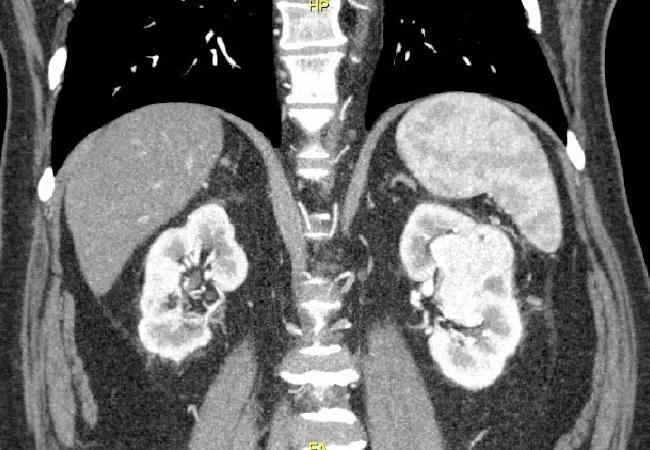

IMmotion151, a phase 3 clinical trial of a new therapy for metastatic renal cell carcinoma (RCC), showed promising results, which were presented at the 2018 American Society of Clinical Oncology (ASCO) Annual Meeting in Chicago. It is one of many recent trials of new treatment regimens that are improving prospects for this once intractable disease.